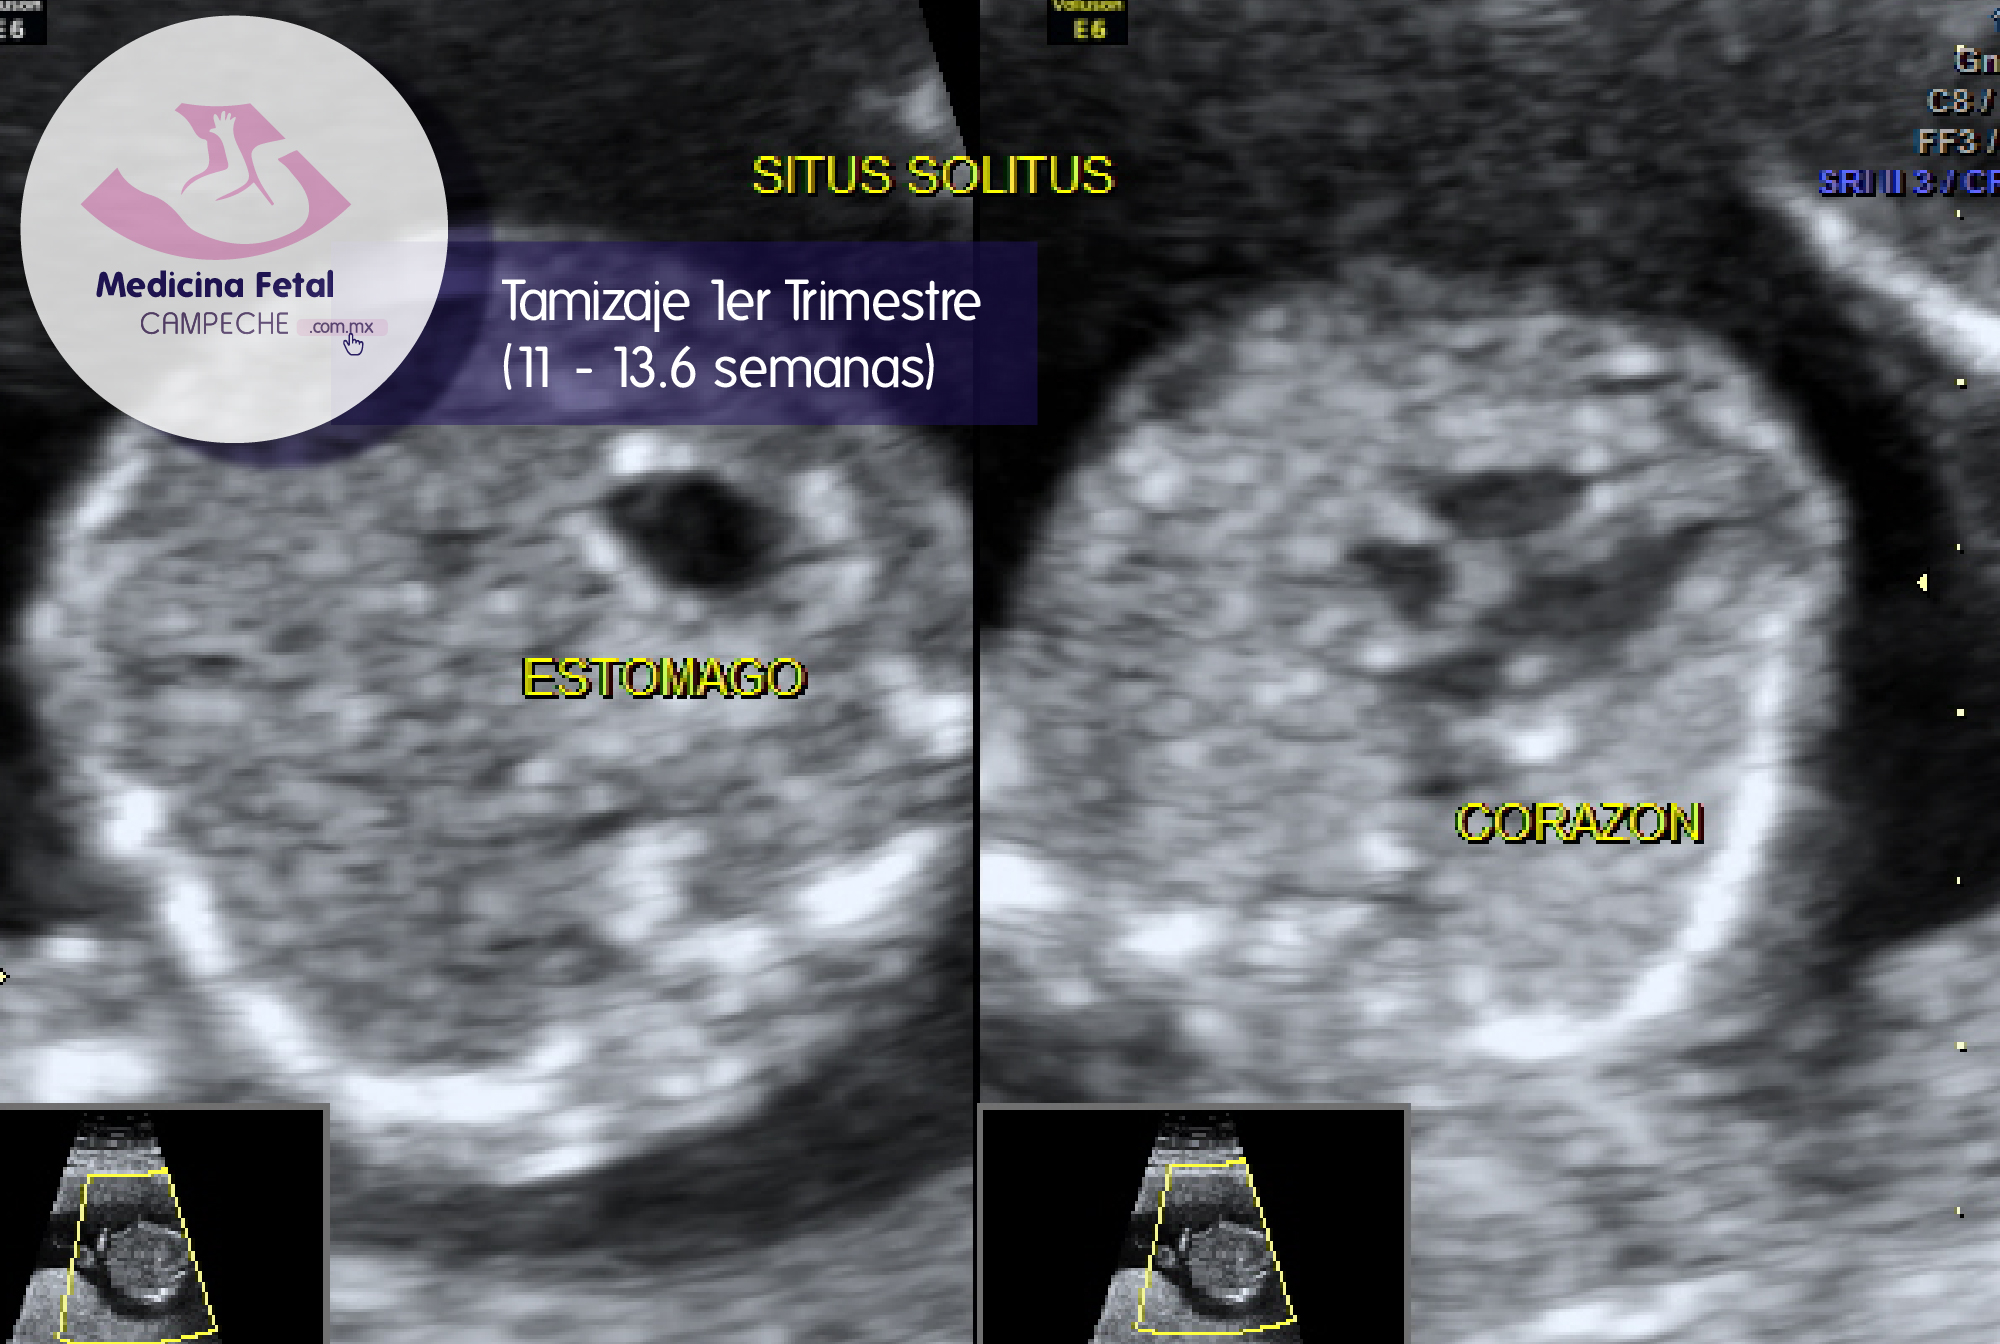

Nos permite además detectar hasta un 80% de anormalidades o malformaciones en los bebés, y de esta manera también emitir un pronóstico sobre la probable evolución del embarazo, y a los padres tomar una decisión sobre el curso de este.

Nos permite además saber cual es la edad exacta de tu embarazo, ya que en estas semanas el ultrasonido tiene su mayor utilidad para tal fin.